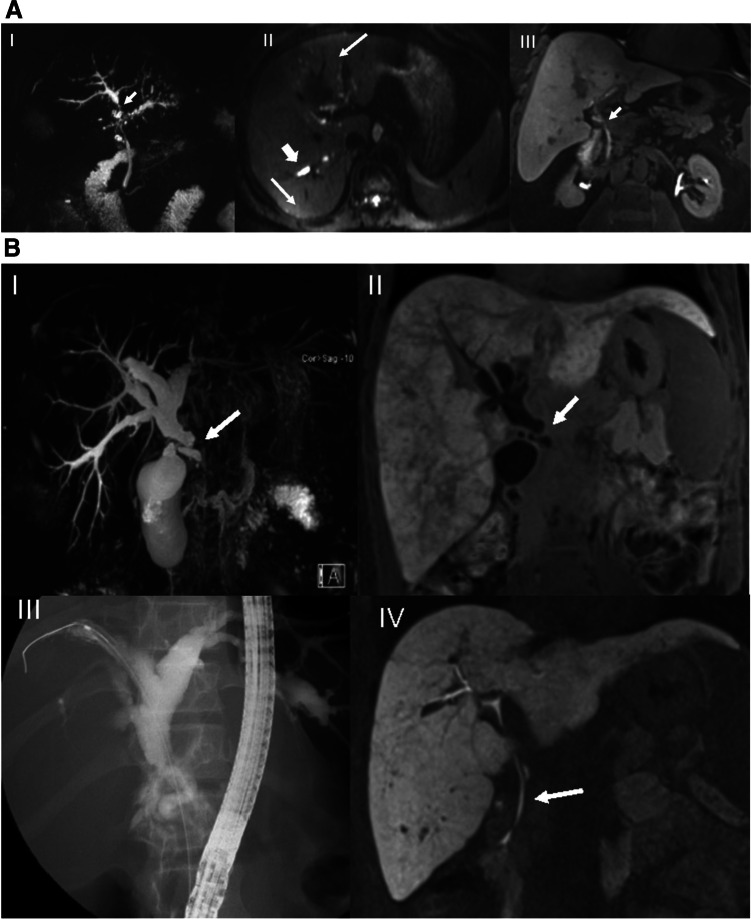

The readers graded intra- and/or extrahepatic bile duct changes on T2-MRCP sequences according to various guidelines, recording the presence of DS or HGS [ref. 5, ref. 24, ref. 29] (Table 3). On 20-min T1-MRC images, patients were stratified into two groups: normal contrast excretion at 20 min (NFS) or impaired excretion (PFS), i.e., no contrast seen either to first-order (LHD or RHD) bile ducts, or CHD/hilum, or CBD or none at all at 20 min (Fig. 2). Then, using multiple-choice format (i.e., RHD, LHD, hilum or CBD), readers were asked to select the location of FS on T1-MRC, and of DS or HGS on T2-MRCP. Stricture location on T1-MRC was determined by the site where contrast media stopped, whereas on T2-MRCP stricture site was assigned to the smallest-diameter segment of the bile duct. Next, they were asked to rate their degree of confidence in stricture location using the Likert scale, where 1 = not confident at all, 2 = slightly confident, 3 = somewhat confident, 4 = fairly confident, and 5 = completely certain.

Finally, we checked for the presence of a secondary malignancy, such as CCA, gallbladder cancer, or HCC. Examples that compare the findings on T1-MRC vs. T2-MRCP are shown in Fig. 3A-C.